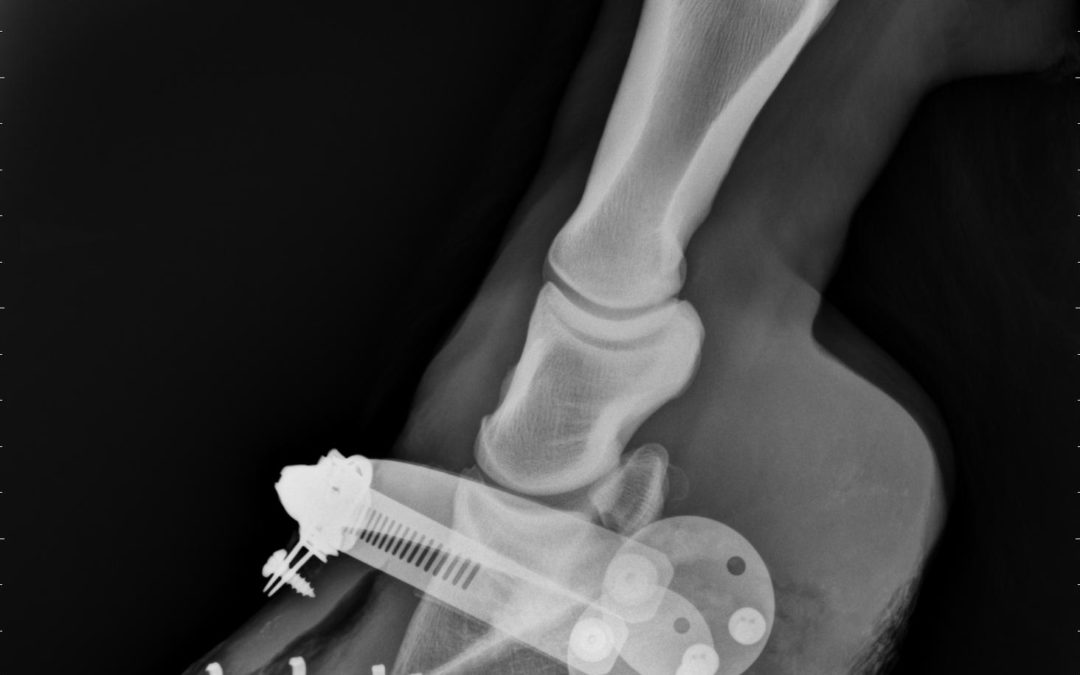

Be-Bop: A Laminitis Tale